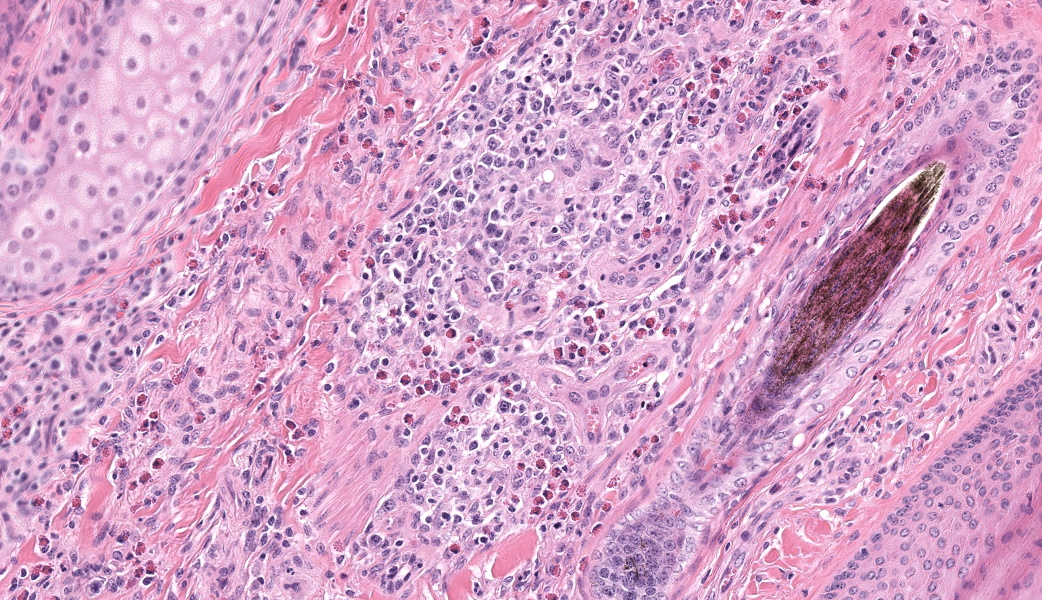

Haired skin, coronary band. Expanding and infiltrating the entire dermis are multifocal to coalescing perivascular, periadnexal and interstitial aggregates of moderate numbers of lymphocytes, eosinophils and histiocytes, fewer plasma cells and occasional neutrophils. Multifocally within dermis are few small areas of intensely eosinophilic, fragmented collagen fibers admixed with eosinophilic cellular- and basophilic nuclear debris, surrounded by epitheloid macrophages and multinucleated giant cells (eosinophilic granulomas). Intramurally and intraluminally within multiple hair follicles are moderate numbers of eosinophils, lymphocytes and histiocytes and few multinucleated giant cells (mural and luminal folliculitis), and adjacent follicular epithelium display moderate spongiosis. In the dermal-epidermal interface, there is a multifocal mild edema. The epidermis shows mild lymphocytic infiltration, mild spongiosis and occasional apoptotic keratinocyte, diffuse mild acanthosis and mild rete ridge formation (epidermal hyperplasia), moderate parakeratotic and orthokeratotic hyperkeratosis and multifocal erosions and ulcerations, the latter being covered by large serocellular crusts spanning over several adnexal units. Serocellular crusts show abundant viable and degenerated neutrophils, occasional eosinophil, cellular debris, fibrin, free keratin and hair fragments and occasional small basophilic bacterial colonies. There are also small epidermal intracorneal pustules multifocally. Several arteriolar walls in deep dermis show infiltration of few eosinophils and lymphocytes (vasculitis). The deep dermis displays mild diffuse edema.Contributor's Morphologic Diagnoses:

Haired skin, coronary band: Dermatitis and folliculitis, lymphoplasmacytic, histiocytic and eosinophilic, multifocal to coalescing, moderate, with eosinophilic granulomas, epidermal intracorneal pustules, serocellular crusts and orthokeratotic and parakeratotic hyperkeratosisEquine multisystemic eosinophilic epitheliotropic disease (MEED)